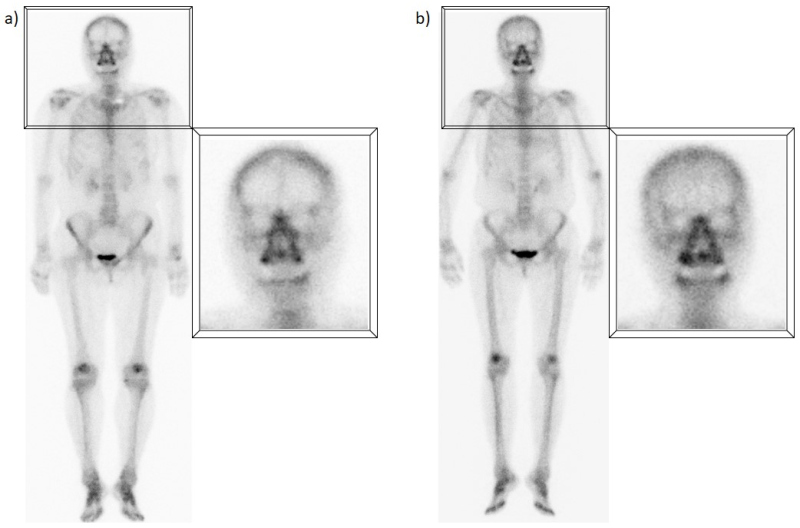

D) Captación del área sino-nasal

Es quizás uno de los hallazgos más frecuentes y su interpretación debe ser cuidadosa, dado que puede representar tanto una patología como una variante normal. A menudo, la captación en la región nasal y maxilar representa la remodelación ósea en las paredes de las cavidades paranasales debido a cambios inflamatorios crónicos(7); esto se ha observado no sólo en pacientes con sinusitis crónica, sino también con rinitis alérgica. Sin embargo, algunos estudios han encontrado que un porcentaje significativo de pacientes (hasta un 42%) sin síntomas respiratorios continúan presentando este patrón de captación, aunque de forma menos prominente(8). En muchos de estos pacientes se ha descrito una captación extra ósea, probablemente secundaria a un mayor flujo sanguíneo y permeabilidad capilar de los tejidos regionales, ya que la mucosa nasal es un área muy vascularizada(9) (fig. 4).

E) Captación esternal

Generalmente este hallazgo se atribuye a cambios degenerativos de las articulaciones esternoclaviculares, bastante frecuentes y que aumentan con la edad, ya que se trata de articulaciones sinoviales que soportan un estrés constante(10). Sin embargo, algunos estudios han descrito patrones de captación normales específicos en el esternón, relacionados con la edad, que no necesariamente representan cambios articulares. Los hallazgos sugieren que una captación difusa, homogénea y leve es normal en pacientes jóvenes, mientras que un patrón más heterogéneo y segmentario, con mayor actividad en los bordes óseos, también puede ser completamente normal en pacientes de edad avanzada(11). Asimismo, la captación focal a nivel de la articulación manubrio-esternal o ángulo de Louis es un hallazgo frecuente, independientemente de la edad, que en la mayoría de los casos puede explicarse por la osificación a nivel de la sínfisis o la presencia de crestas óseas (fig. 5).